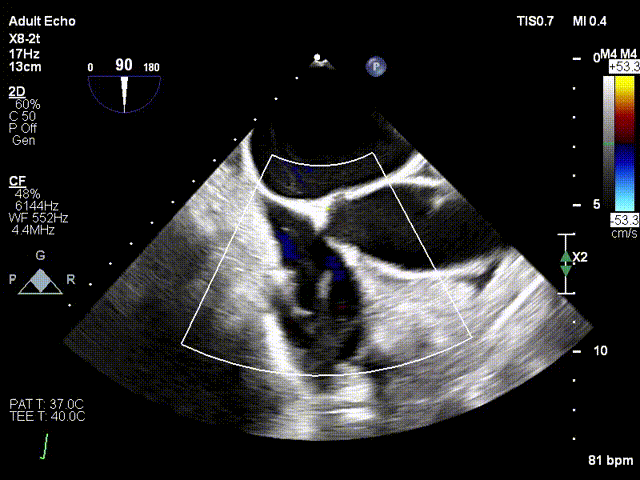

1. 术中基线评估三尖瓣反流程度

术中基线

5. 夹合后反流评估

反流

术前术后反流对比:三尖瓣反流4+下降至1+

术前反流

术后反流